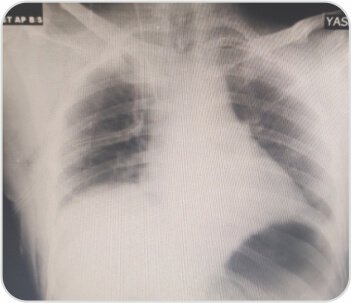

CXR showed right sided pneumothorax. ICD was placed. CT scan showed apical bullae. Uniportal bullectomy was done by Video-assisted thoracoscopic surgery (VATS).

CXR at the time of discharge on POD 3